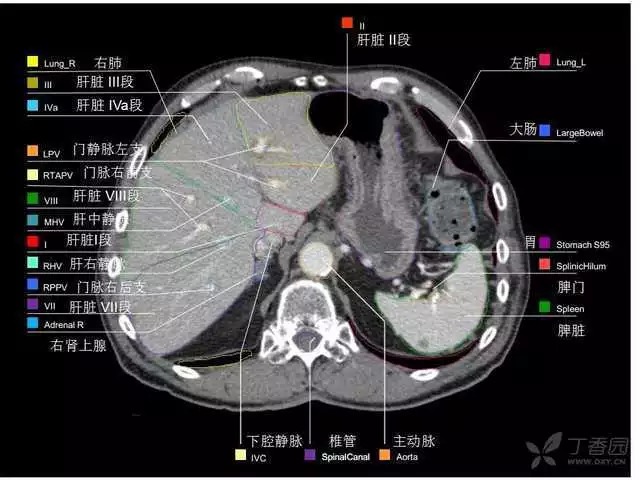

腹部肝脏高清CT断层的图谱

全腹部高清CT图谱,淋巴结彩色图谱,血管解剖图谱大汇总!

肝段,肝内管道的分布规律

美国放射学会ACR官网,对肝脏的区域和节段解剖学概述